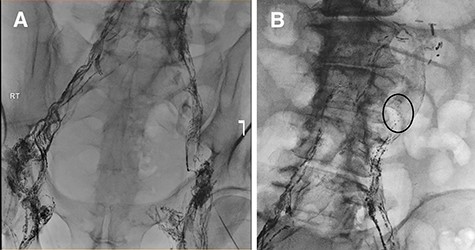

On postoperative Day 5, diet was resumed and the patient subsequently developed abdominal distention, for which a computer tomography scan was performed (Fig. 1a and b). Therapeutic paracenteses confirmed chylous ascites and he was placed on total parenteral nutrition (TPN) and octreotide. Despite conservative management, the ascites re-accumulated on resumption of oral intake.

Coronal (A) and axial (B) sections of non-contrast enhanced abdominal computed tomography showing accumulation of large volume of peritoneal fluid. Aortic graft appears intact.